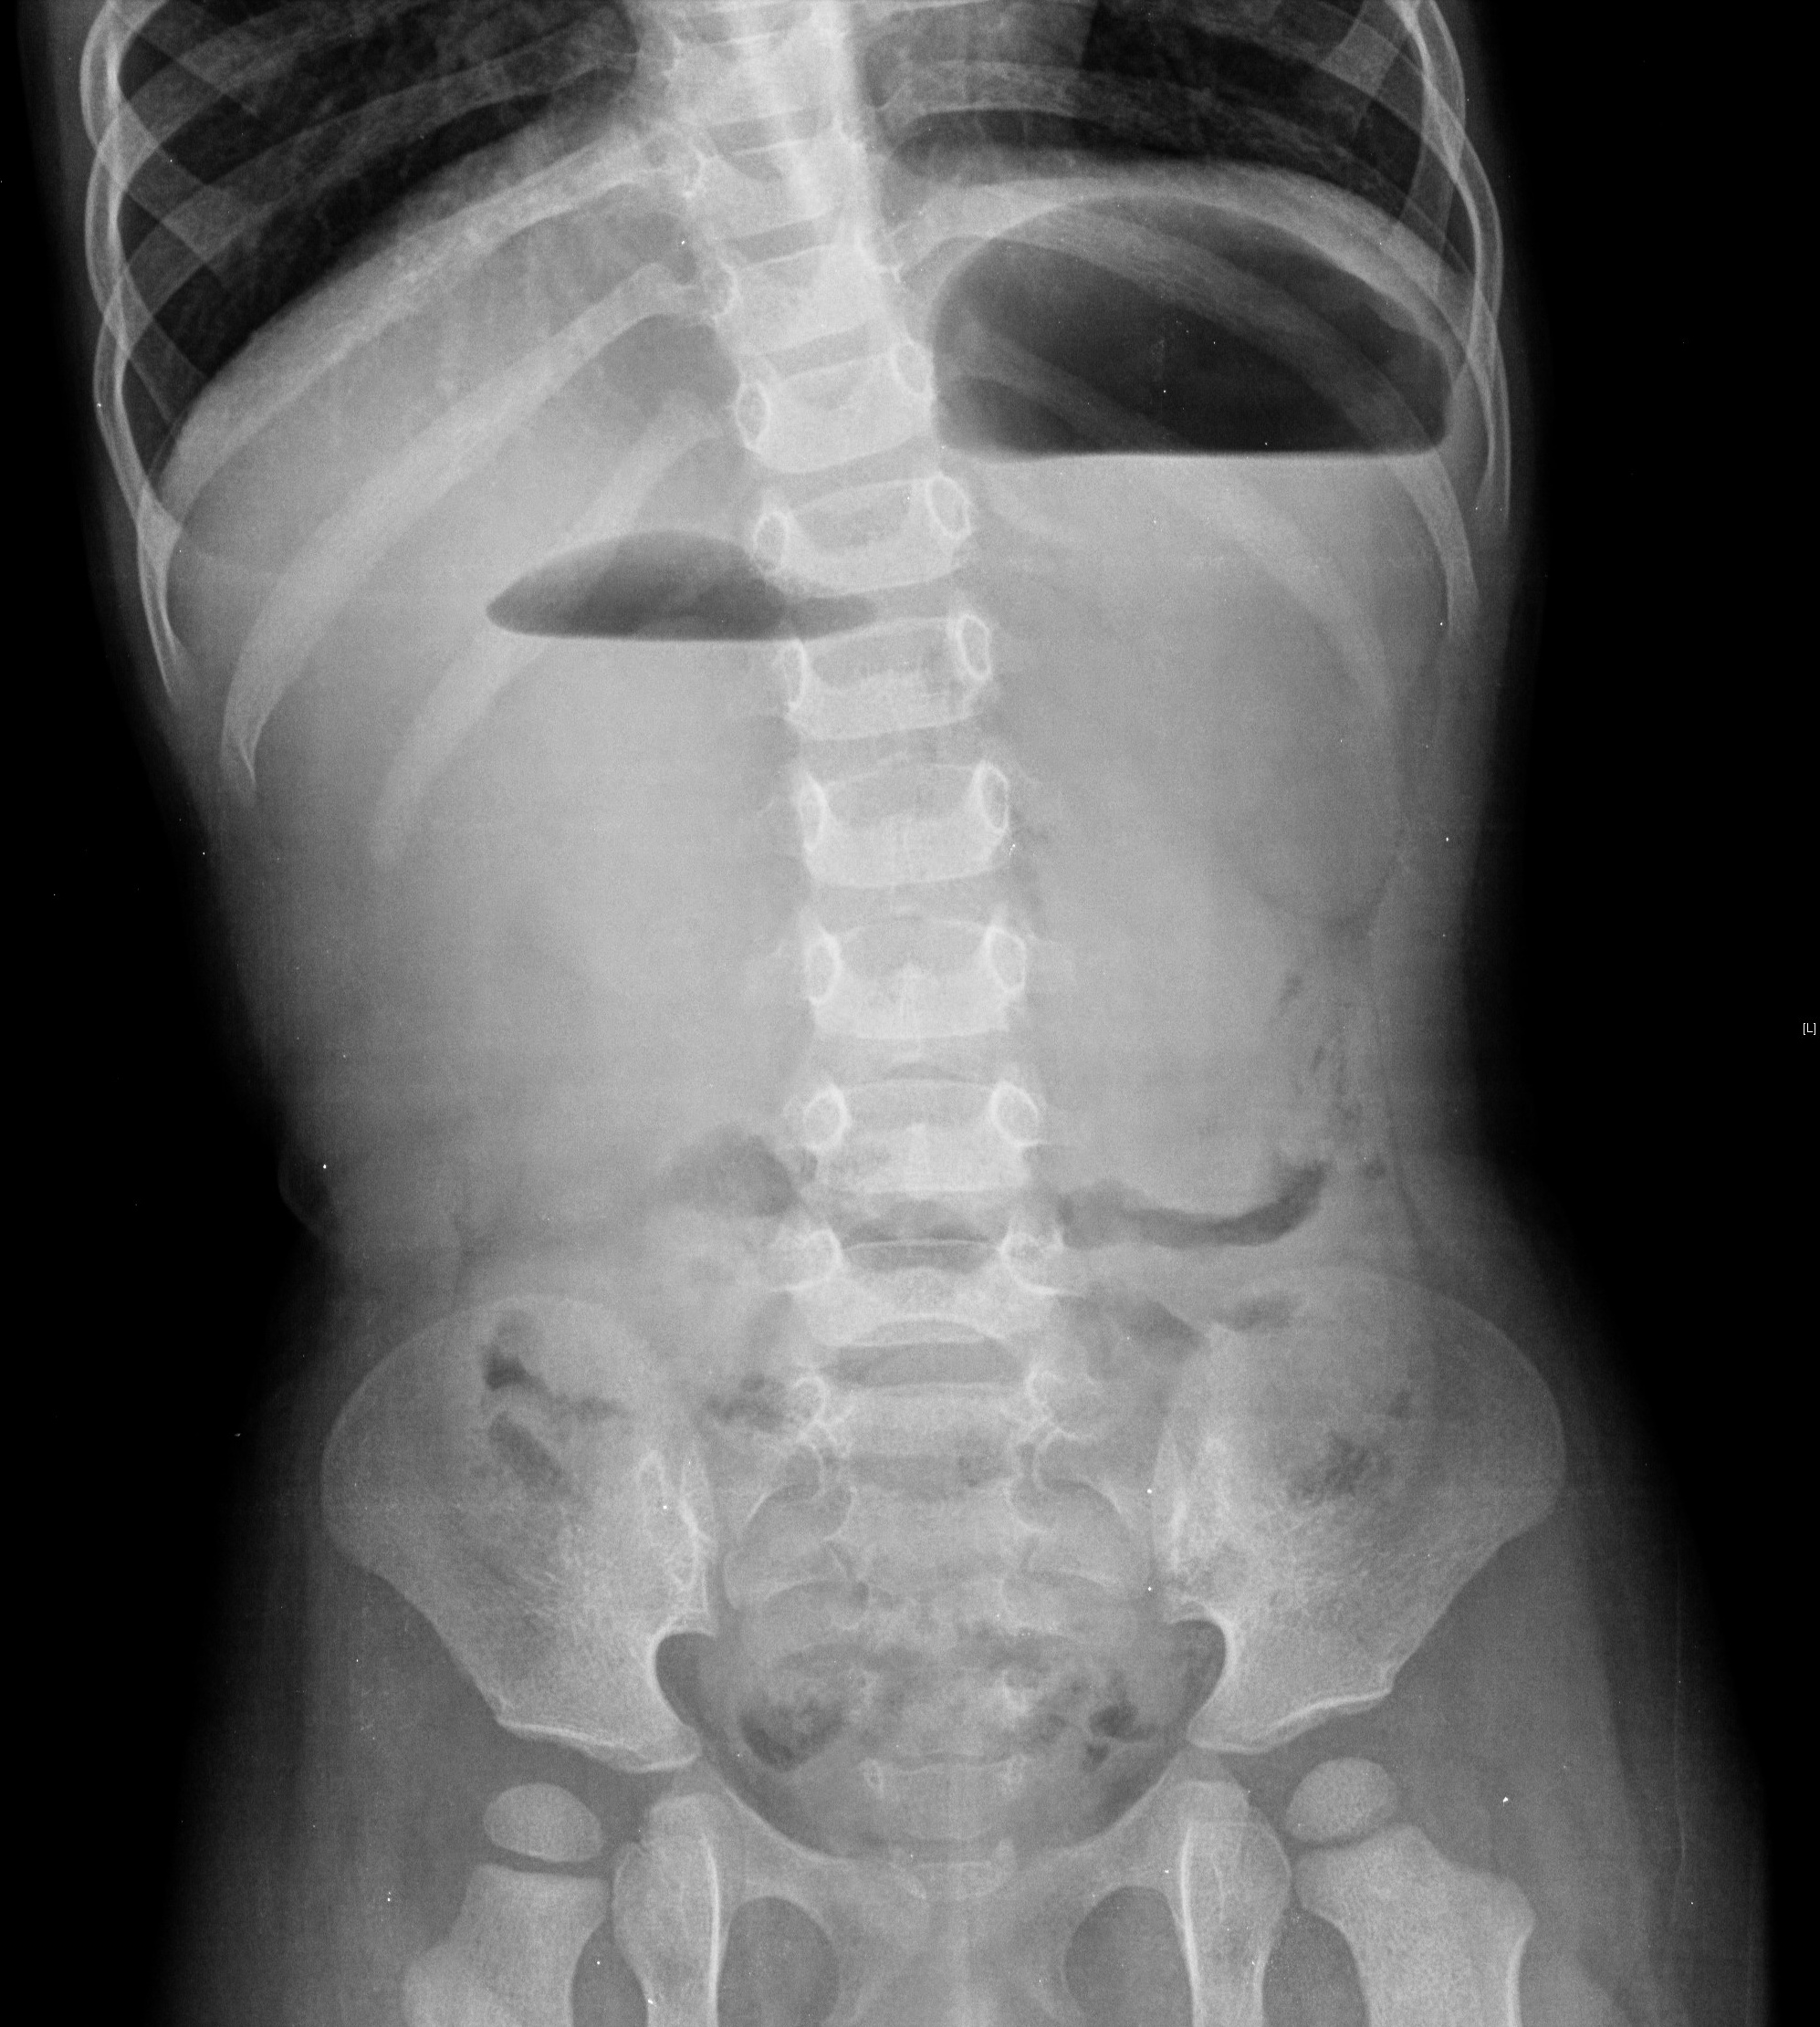

A obstrução duodenal congénita, secundária a atresia ou estenose, tem tipicamente apresentação no período neonatal com sinais de oclusão intestinal alta. Todavia, uma apresentação mais tardia e diversa pode ocorrer nos raros casos de obstrução parcial do duodeno devido à presença de uma membrana duodenal perfurada, colocando sérios desafios no seu diagnóstico.Reportam-se três casos clínicos de obstrução duodenal congénita com apresentação após o período neonatal. Os três casos partilham uma história de vómitos recorrentes e má progressão ponderal com início após a diversificação alimentar. A identificação de achados radiológicos específicos, tais como os sinais de dupla bolha e de wind sock, foi determinante para o diagnóstico.A obstrução duodenal congénita devido à presença de uma membrana duodenal perfurada é uma entidade rara e o seu reconhecimento nem sempre imediato. Uma história clínica minuciosa, aliada a achados radiológicos específicos, constitui a chave para um diagnóstico atempado dos casos de obstrução duodenal congénita com apresentação tardia.